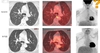

Pulmonary nodule uptake

A

Pneumonia

Tuberculosis

Cryptococcosis

Histoplasmosis

Sarcoidosis

Radiation pneumonitis

Pleurodesis